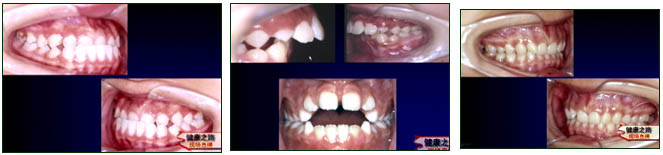

主持人:治疗效果如何? 张丁:来看几个病例:如图患者的牙齿排列很乱,治疗后牙齿的排列非常整齐。另一张图中,地包天的患者通过治疗后,咬合关系和脸形都恢复了正常。 贾绮林:矫正牙齿是把牙齿矫正到了一个新的位置上,由于牙齿有一个回到原来位置的趋势即复发,通常是运用保持器来防止复发,保持器可以很好的维持牙齿的新位置,一般需要戴两年,第一年需要24小时戴(吃饭、刷牙除外),第二年一般是晚上戴,对于一些特殊的畸形,根据不同的情况,配戴的具体要求也不一样。